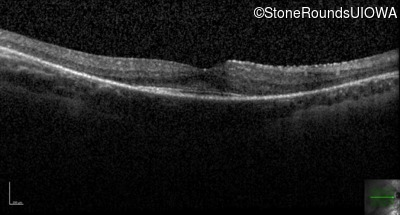

Optical Coherence Tomography - Right - 20/20 sc

Exemplar / OCT Stack

OCT Stack